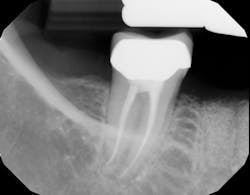

Although unpredictable, a greater amount of alveolar ridge loss following extraction usually occurs in the horizontal dimension and affects the buccal bone of the ridge.3 In fact, 50% of alveolar bone dimension can be lost after tooth extraction, with losses reported of up to 6–7 mm (figure 1). Two-thirds of this loss of bone volume can occur within the first three months of tooth extraction.4

Because of this alveolar resorptive pattern after tooth extraction, bone grafting the extraction socket after tooth extraction procedures has become a solution that attempts to limit the amount of hard- and soft-tissue loss. There are many systematic reviews in the literature that compare the results of residual ridge dimension following tooth extraction after the use of a bone graft (with or without a membrane) versus extraction alone without grafting.7